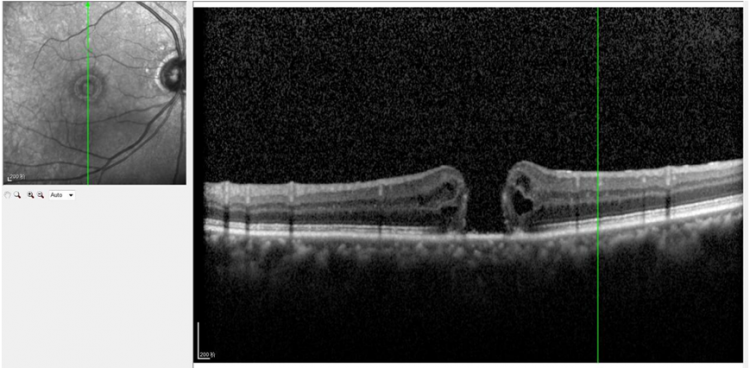

眼底病眼外伤科